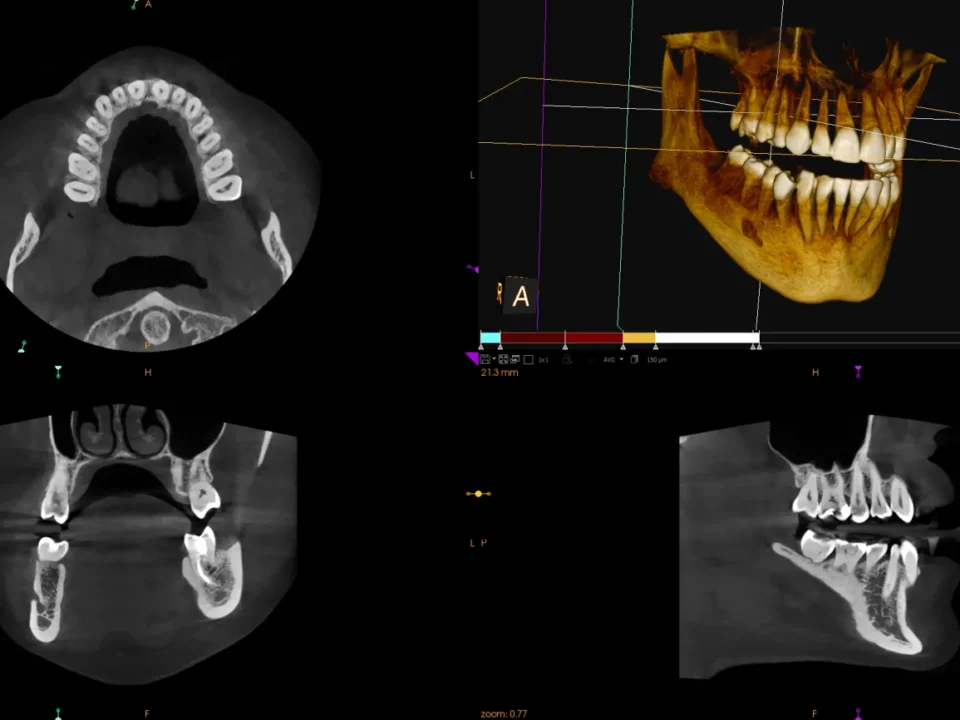

Tomograf stomatologiczny, czyli TK, jest zaliczany do najdokładniejszego i rozstrzygającego badania RTG. Jakie wady i dysfunkcje wykaże tomografia komputerowa zębów? Jaka jest cena za takie badanie? Czym jest tomografia stomatologiczna? Tomografia stomatologiczna, funkcjonująca także pod skrótową nazwą TK, to rodzaj […]